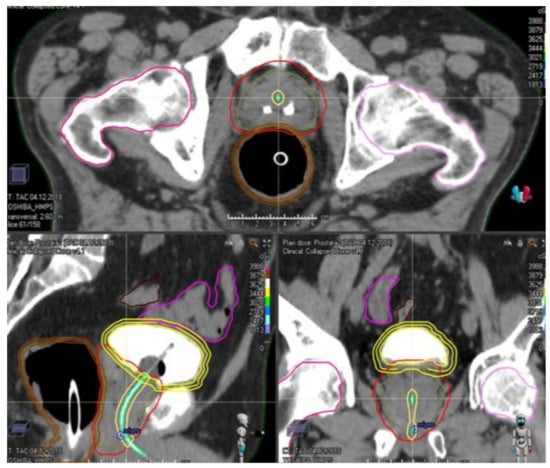

5. Contribution of Endorectal Devices in Prostate SBRT

- Yoon, S.; Cao, M.; Aghdam, N.; Shabsovich, D.; Kahlon, S.; Ballas, L.; Collins, S.; Steinberg, M.L.; Kishan, A.U. Prostate bed and organ-at-risk deformation: Prospective volumetric and dosimetric data from a phase II trial of stereotactic body radiotherapy after radical prostatectomy. Radiother. Oncol. 2020, 148, 44–50. [Google Scholar] [CrossRef]

- Dubouloz, A.; Rouzaud, M.; Tsvang, L.; Verbakel, W.; Björkqvist, M.; Linthout, N.; Lencart, J.; Pérez-Moreno, J.M.; Ozen, Z.; Escude, L.; et al. Urethra-sparing stereotactic body radiotherapy for prostate cancer: How much can the rectal wall dose be reduced with or without an endorectal balloon? Radiat. Oncol. 2018, 13, 114. [Google Scholar] [CrossRef]

- De Leon, J.; Jameson, M.G.; Rivest-Henault, D.; Keats, S.; Rai, R.; Arumugam, S.; Wilton, L.; Ngo, D.; Liney, G.; Moses, D.; et al. Reduced motion and improved rectal dosimetry through endorectal immobilization for prostate stereotactic body radiotherapy. Br. J. Radiol. 2019, 92, 4–11. [Google Scholar] [CrossRef] [PubMed]